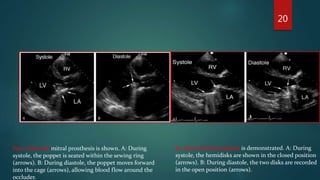

St. Jude mitral prosthesis is demonstrated. A: During

systole, the hemidisks are shown in the closed position

(arrows). B: During diastole, the two disks are recorded

in the open position (arrows).

Starr-Edwards mitral prosthesis is shown. A: During

systole, the poppet is seated within the sewing ring

(arrows). B: During diastole, the poppet moves forward

into the cage (arrows), allowing blood flow around the

occluder.

St. Jude mitralprosthesis is demonstrated. A: During systole, the hemidisks are shown in the closed position (arrows). B: During diastole, the two disks are recorded in the open position (arrows). Starr-Edwards mitral prosthesis is shown. A: During systole, the poppet is seated within the sewing ring (arrows). B: During diastole, the poppet moves forward into the cage (arrows), allowing blood flow around the occluder. 20